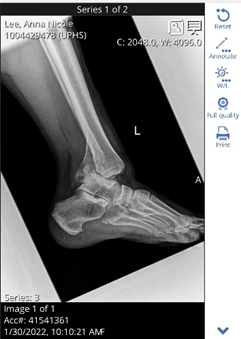

And then I fell in excruciating pain, not knowing how I was going to get back up and wondering if maybe one of the dogs could tell a neighbor, “Suzie’s stuck in the well and my Momma Nicole’s face is stuck to the stairs. Thankfully, Willow, my savior and friend found me, and I was rushed to the emergency room. The ER doctor found that I had a P line, fibula and tibia fracture.

Check out this fun picture. Something here doesn’t seem right…hmmm

On Friday January 11, I received two plates and 13 screws in my left ankle. I have returned to the rehab facility where I have spent five weeks learning how to move around and be able to go home.